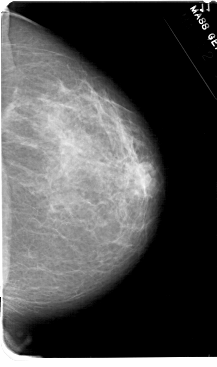

A_1607_1.LEFT_MLO

LEFT_MLO LINES 5491 PIXELS_PER_LINE 3406 BITS_PER_PIXEL 12 RESOLUTION 43.5 OVERLAY